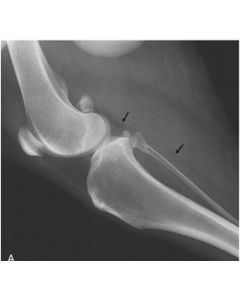

This video is part of a series of instructional videos designed to help new and experienced laser users effectively deliver laser therapy to specific joints. This video looks at that most challenging of joints, the stifle.